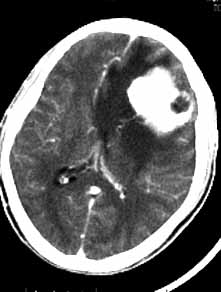

脑膜瘤03

男性,36岁,头痛数年,近期伴有视蒙。

ct诊断:左额颞部脑膜瘤。